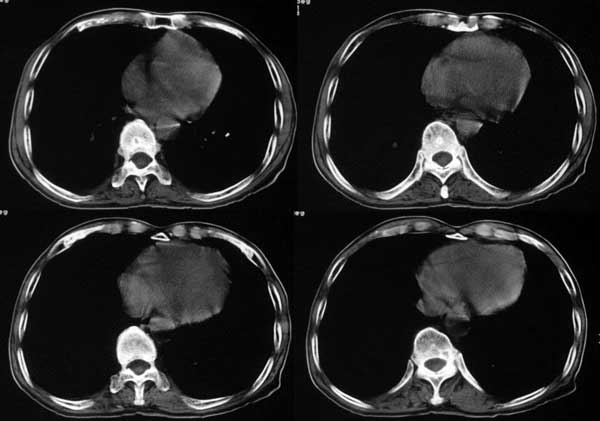

患者,男79岁,左侧肾癌术后5个月。近三个月,咳嗽时有痰中带血。

附肾脏平扫及增强片

手术是怎么做的,好像没做。右肾还有两个病灶。气管腔内的那个结节密度确实很低,考虑粘痰核应该没问题,若是新生物不会这么低。不过挂在前壁上了,少见!

肺及胸膜下多发结节影,胸椎及附件、肋骨破坏支持转移癌。气管内结节影支持痰核。肾脏ct应该是术前的吧?左肾内亦见一低密度灶,另外胰腺好像也不规则。不知术后结果如何?

左侧肾癌,腹膜后淋巴转移,肺及胸椎转移,右肾转移可能,气管内痰栓可能[壁可见]